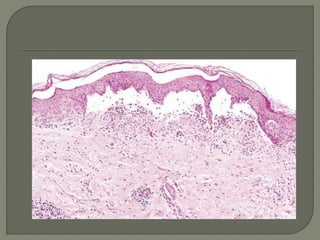

 Serous inflammation is marked by the

skin blister resulting from a burn or viral

infection represents a large accumulation of

serous fluid, either within or immediately

beneath the epidermis of the skin

 Serous inflammationis marked by the outpouring of a thin fluid that may be derived from the plasma or from the secretions of mesothelial cells lining the peritoneal, pleural, and pericardial cavities. Accumulation of fluid in these cavities is called an effusion. The skin blister resulting from a burn or viral infection represents a large accumulation of serous fluid, either within or immediately beneath the epidermis of the skin